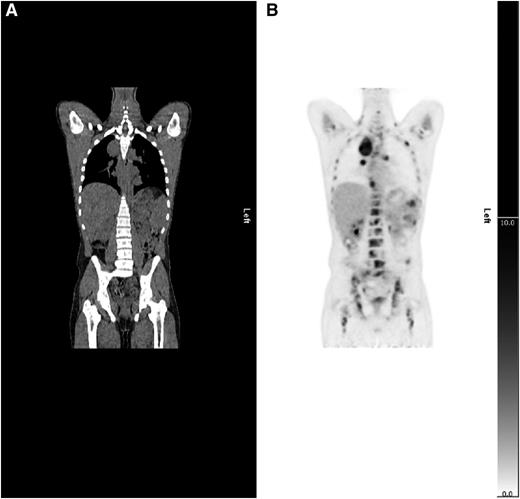

There was agreement between the RATHL stage and the PET-CT stage in 938 (80%) patients. A total of 159 patients (14%) were upstaged and 74 patients (6%) were downstaged by PET-CT (Table 1). The main reason for upstaging was detection of extranodal disease (Table 2), most commonly in bone marrow (Figure 2). Upstaging due to nodal involvement also occurred, mostly below the diaphragm (Table 2). Reasons for downstaging included enlarged nodes and/or spleen, which were not FDG-avid and extranodal sites with abnormal morphology but no FDG uptake (Table 2).

Example of upstaging by PET-CT. (A) CT and (B) PET coronal images show a case upstaged by PET-CT. Nodal and splenic involvement was reported on CT and interpreted as stage 3. The PET scan showed multifocal uptake in bone marrow upstaging to stage 4.